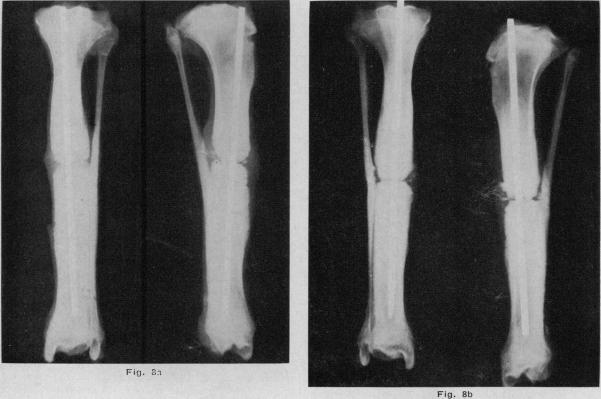

The effect of heat on the healing of fractures: a preliminary experimental report.

Can Med Assoc J. 1967 Aug 5;97(6):274-80.